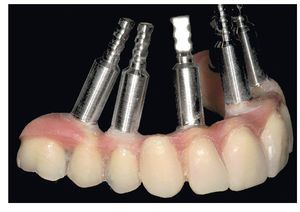

Fig. 65. Los implantes en el maxilar superior, integrados mediante técnica sin colgajo, y los pilares correspondientes para prótesis atornilladas.

Fig. 69. Los implantes y las cofias provisionales para prótesis atornilladas colocados en el maxilar inferior.

La intervención quirúrgica (figs. 63 y 64) se realizó bajo anestesia local y se trataron al mismo tiempo ambas arcadas dentarias. Durante la primera fase se insertaron seis implantes cónico-cilíndricos (SPI®CONTACT, Thommen Medical AG, Waldenburg, Suiza) en la arcada dentaria superior mediante un acceso sin colgajo. Para ello se utilizaron los pilares pertinentes para reposiciones de puente atornilladas oclusalmente (VarioMulti, Thommen Medical AG, Waldenburg, Suiza) (fig. 65). Tras la intervención quirúrgica se colocó en boca la prótesis provisional prefabricada a partir de los datos de planificación y tallada en las posiciones de implante y se unió a las cofias provisionales (fig. 66 y 67); para ello se utilizó un composite de fraguado dual. Mediante una prótesis provisional mucosoportada se pudo preservar la estructura gingival hasta el momento de la implantación, y con ello la relación correcta entre los maxilares superior e inferior. Para la arcada dentaria inferior se utilizaron implantes cilíndricos (Element, Thommen Medical AG) (figs. 68 y 69). En combinación con los pilares pertinentes para prótesis atornilladas, se procedió aquí de la misma manera que en el maxilar superior. Una vez se hubo alineado oclusalmente la prótesis provisional del maxilar inferior con respecto al superior, se fijó sobre las cofias provisionales (fig. 70); debido a la formación de colgajo no había sido posible la alineación sobre la mucosa. Este procedimiento permite preservar la dimensión oclusal vertical que se definió al principio del tratamiento. A continuación se repasan, se pulen y se envían a la clínica para su incorporación las prótesis provisionales, las cuales, por el contrario, se apoyan exclusivamente sobre los implantes (figs. 71 y 72). Allí tienen lugar el control radiológico y el rectificado oclusal (figs. 73 y 74).